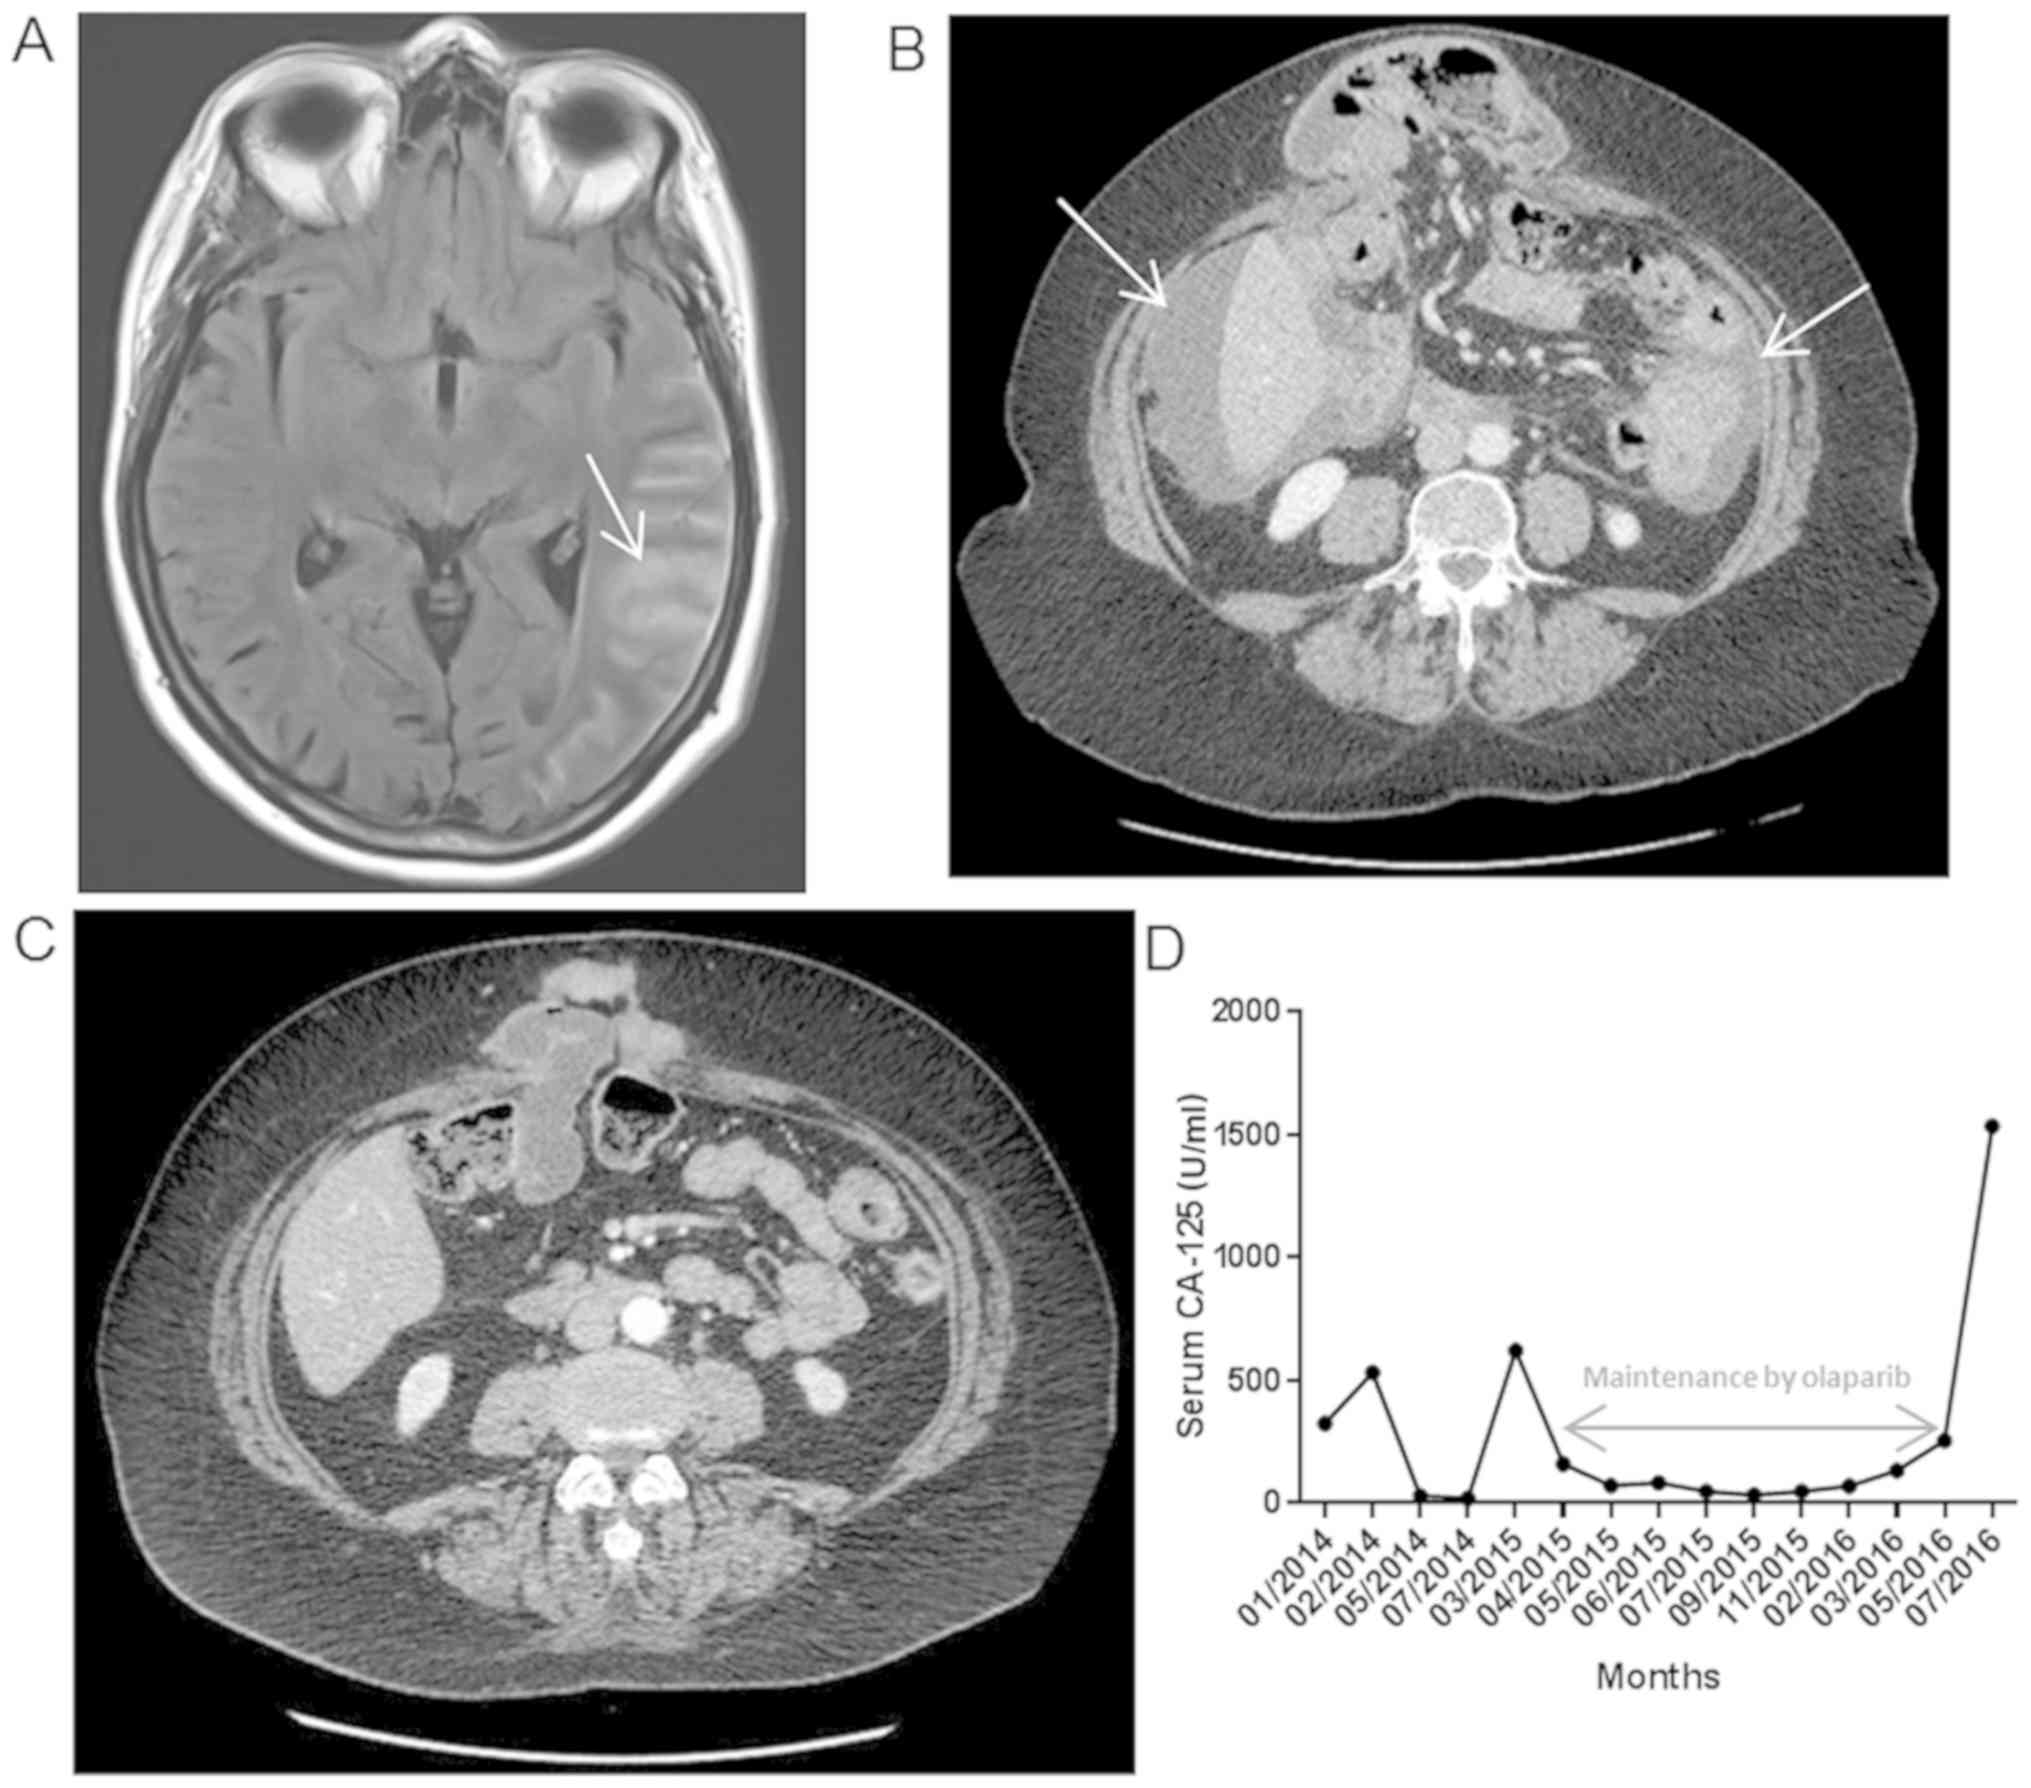

Six months later, patient complained of headaches, and magnetic resonance imaging (MRI) revealed nodular meningitis (Fig. 1A). Lumbar puncture confirmed carcinomatous cell presence. Additionally, computed tomography (CT) scan showed peritoneal progression (Fig. 1B) without other lesions.

Figure 1

Imagery and biological exams performed throughout medical care. (A) MRI showing nodular meningitis (white arrow). (B) CT scan exam indicating the presence of an abundant ascites liquid quantity (white arrows). (C) CT scan exam showing the complete disappearance of ascites after platin-based chemotherapy. (D) Serum CA-125 dosage throughout the maintenance by olaparib treatment. MRI, magnetic resonance imaging; CT, computed tomography.

Genomic DNA from meningeal cells was fragmented with a Covaris device to obtain fragments around 180-200 bp. Subsequently, libraries were constructed and captured by using SureSelect Human All Exon v5 kit (Agilent Technologies, Inc.) following manufacturer's protocol. Paired-end (2x151 bases) sequencing was performed on a NextSeq500 device (Illumina, Inc.). Obtained sequences were aligned and annotated with the human Hg19 genome based on SureSelect Human All exon v5 manifest by using BWA and GATK algorithms. Only sequences with a read depth of 10X and a mutation allele frequency superior to 5% were analyzed. Exome analysis on meningeal cells confirmed the presence of the pathogenic BRCA2 mutation. Moreover, the tumor homozygous pathogenic BRCA2 mutation status (mutated allele frequency of 98%) suggested a loss of wild-type allele in tumor cells. Whole brain radiotherapy was carried out and Cisplatin monotherapy treatment was administrated from March to June 2015. CT scan confirmed a positive response to chemotherapy (Fig. 1C) and Olaparib treatment was proposed. This treatment allowed a 14 month disease control (Fig. 1D) with a good quality of life. Standard dose was administered without any modification due to excellent tolerance.